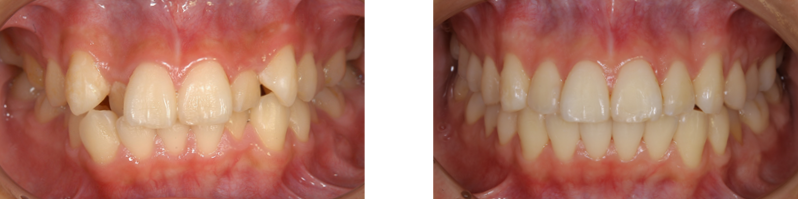

矯正治療は歯並びの不正や、かみ合わせを治療しますが、見かけをきれいにするだけでなく、 成長期の子供であれば、適正な顎顔面の成長発育を促し、成人であれば、咬合崩壊の予防、改善を促す治療です。

歯を中心としたかみ合わせ、発音、咀嚼器官、機能の回復、顔の形態、コンプレックス等、全身の健康に影響を及ぼす治療分野でもあります。

咬み合わせの改善

良いかみ合わせは上下の歯が単に噛み合うだけでなく、顎の関節と調和して機能し、全身のバランスもとれている状態のことです。 かみ合わせに問題が生ずると、歯に悪い影響が現れるだけでなく、顔の歪み、顎関節炎などによる開口障害、偏頭痛、肩こり、耳鳴りなどの影響がでる場合もあります。

見えない矯正装置(舌側矯正)

当院では、見えない矯正(舌側矯正)を主に行なっております。メリットは矯正装置を歯の裏側に装着することで外から目に触れないということです。